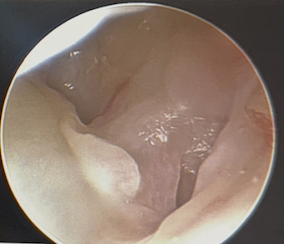

Technique arthroscopic repair

Ulna / foveal sided TFCC tear on arthroscopy

Technique

- viewing via 3-4 portal

- instrumentation via 6R +/- 6U portal (either side of ECU)

- pass outside in and suture over capsule

- suture anchor repair

- drill hole in ulna